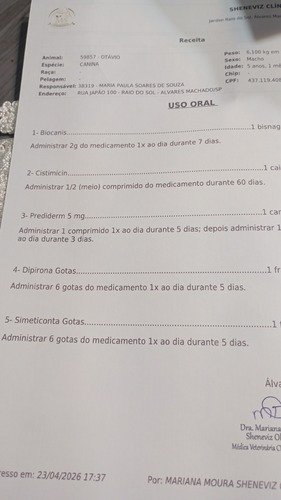

Olá pessoal, eu sou o Otávio tenho 6 aninhos, fui achado em uma estrada de sítio abandonado, fui resgatado , não encontrado dono e acabei sendo adotado. Comecei a andar curvado, de não conseguir andar, barriga bem distendida e fui levado ao veterinário, porém foi feito vários exames e deu fezes retidas a ponto da dor ser intensa e não andar, também infecção de urina, o tratamento ficou caro e peço a ajuda de vocês com qualquer quantia que tocar no seu coração. Agradeço imensamente.